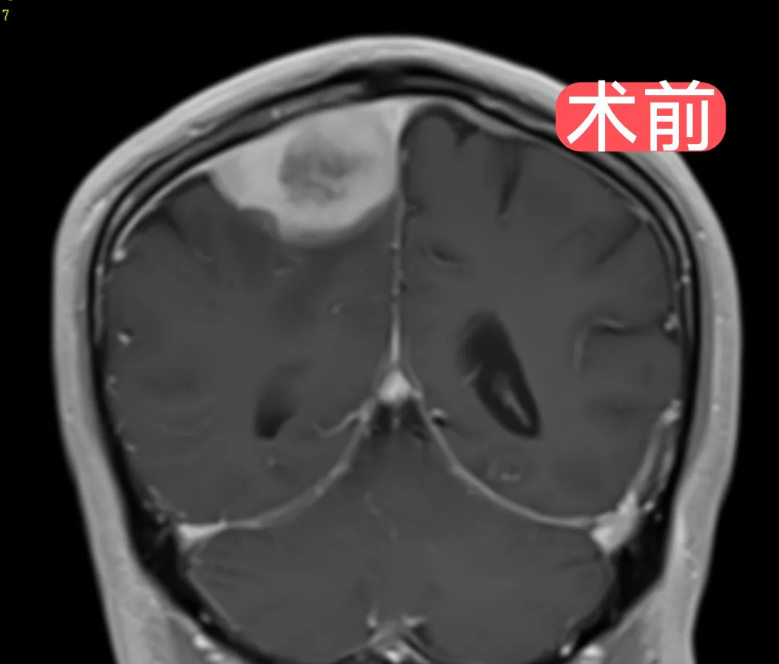

患者因"左肢体乏力"来院就诊,经检查确诊为"中央区矢状窦旁脑膜瘤"。这个直径约6cm的肿瘤位置极为凶险,不仅位于大脑中央功能区,还侵犯了矢状窦这一大脑主要静脉通道,被重要血管紧密包裹。

面对这一严峻挑战,神经外科团队迎难而上。术前运用先进的3D数字规划与3D打印技术,对肿瘤及周围组织进行三维建模,精准还原解剖关系,制定个性化手术方案。

手术过程中,在欧海荣主任医师的指导下,由李越主任医师领衔主刀,李辉副主任医师、陈思医师默契配合。团队在显微镜下以"抽丝剥茧"般的精细操作,完整剥离肿瘤,并成功修补重建受侵犯的矢状窦,全程完好保护周围脑组织与重要血管。